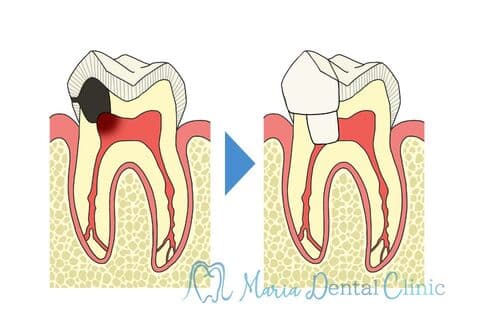

【初回根管治療(抜髄)神経をとる

治療】

初めて歯の神経(歯髄)を取り除く処置です。歯髄炎の症状は抜髄処置を施すことで改善されます。また、根管内の細菌感染が再根管治療よりはまだ少ないので、治療の成功率が高い時期でもあります。根尖性歯周炎の罹患を最小限にすると同時に再根管治療を不要にすることで将来的に歯を最大限保存することにつながるため、再根管治療に比べると精密根管治療の費用対効果が高くなります。